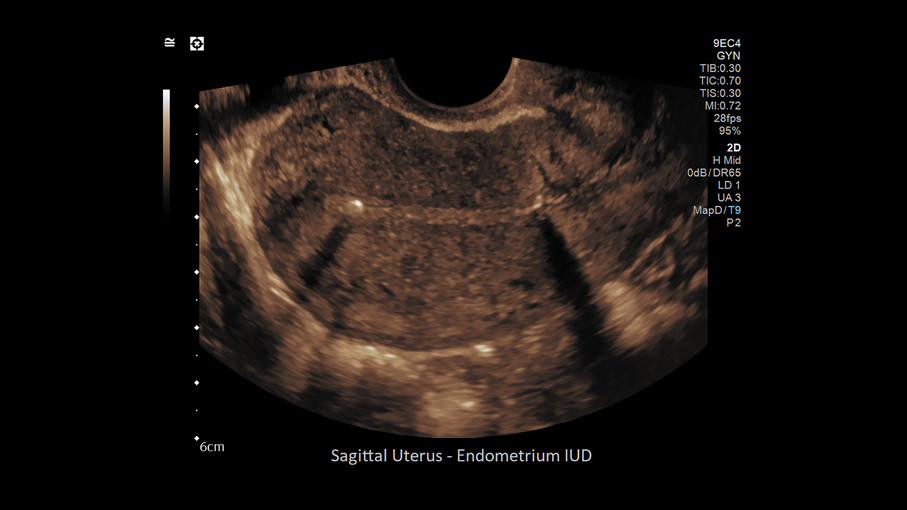

Кроме новой техники, можно заказать восстановленные медицинские системы: ультразвуковые сканеры, томографы, флюороскопы, ангиографы и хирургические установки С-дуга.